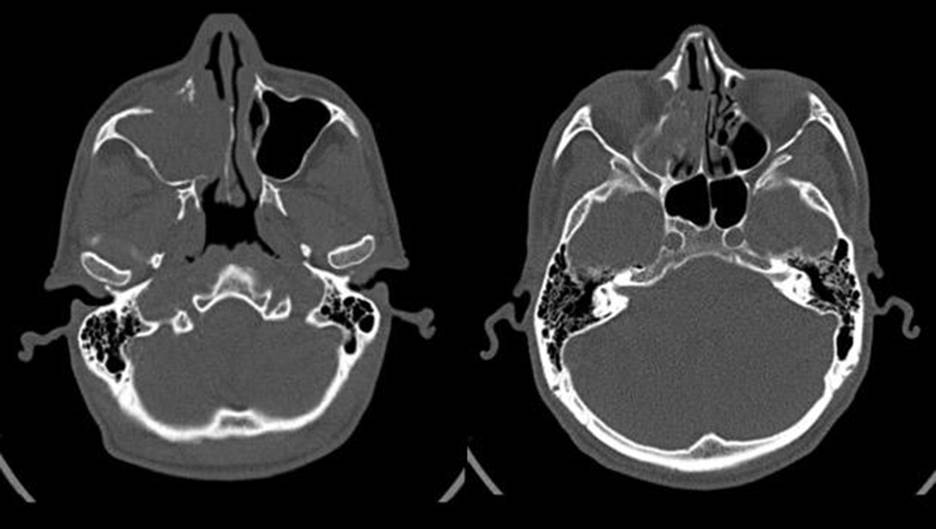

Bệnh nhân nam 48 tuổi, vào viện vì triệu chứng chảy máu mũi kèm nghẹt mũi bên phải kéo dài đã lâu. Bệnh nhân không có tiền sử chấn thương vùng hàm mặt và các bệnh lý khác kèm theo. Qua thăm khám lâm sàng và nội soi mũi họng phát hiện một khối u lớn ở hốc mũi phải. Hình ảnh CLVT cho thấy khối lớn ở xoang hàm phải, phá hủy thành xoang và xâm lấn rộng vào hốc mũi và xoang sàng cùng bên. Trên hình ảnh cộng hưởng từ, khối u này lấp đầy xoang hàm phải, xâm lấn xoang sàng và hốc mũi, xương hàm trên, ngấm thuốc mạnh, gợi ý khối u ác tính, giàu mạch từ xoang hàm phải. Bệnh nhân được sinh thiết khối u với chẩn đoán là carcinoma dạng vảy kém biệt hóa xâm lấn từng ổ. Tuy nhiên, trong và sau sinh thiết khối u chảy máu nhiều. Sau khi hội chẩn giữa chuyên khoa TMH và CĐHA can thiệp, đánh giá khối u lớn, xâm lấn rộng, tăng sinh mạch, nguy cơ chảy máu nhiều và khó kiểm soát trong lúc phẫu thuật, bệnh nhân được chỉ định nút mạch nuôi u trước mổ nhằm giảm thiểu lượng máu mất và nâng cao hiệu quả cuộc phẫu thuật. Trước khi can thiệp nội mạch, bệnh nhân được chụp CLVT mạch máu để xác định nguồn mạch nuôi u.

Hình 1: Khối u lớn ở xoang hàm phải, phá hủy thành xoang và xâm lấn rộng vào hốc mũi và xoang sàng cùng bên